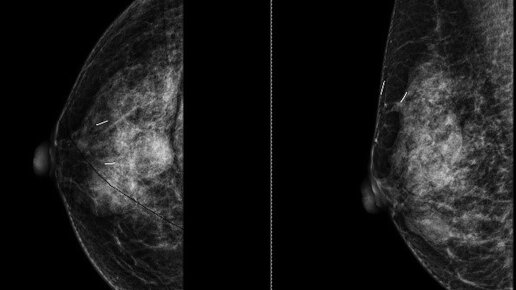

Что это такое? Компьютерная томография – это мощный рентген, который делает множество снимков-срезов за доли секунды. Компьютер собирает их в 3D-модель. Для исследования сосудов используют контрастное вещество на основе йода.

1. Кальций в коронарных артериях (Коронарный кальциевый скор, Agatston score). Это ключевое отличие от УЗИ и МРТ. КТ без контраста может количественно измерить кальций – прямой признак атеросклероза. Результат – цифра. 0 – идеально, 1-100 – минимальные бляшки, >400 – выраженный атеросклероз, высокий риск.

2. КТ-коронарография (с контрастом): Показывает просвет артерий в 3D. Врач видит не просто бляшку, а насколько она сужает сосуд (например, "гемодинамически значимый стеноз 70% в передней нисходящей артерии").

3. Анатомия: Точные размеры камер, аномалии развития (например, дополнительные сосуды), состояние крупных сосудов (аорты, легочной артерии).

Плюсы: Невероятная детализация анатомии, самое быстрое исследование (одна задержка дыхания), лучший метод для оценки кальция и стентов/шунтов.

Минусы: Лучевая нагрузка (хоть и малая), необходимость вводить контраст (риск аллергии на йод, нагрузка на почки).